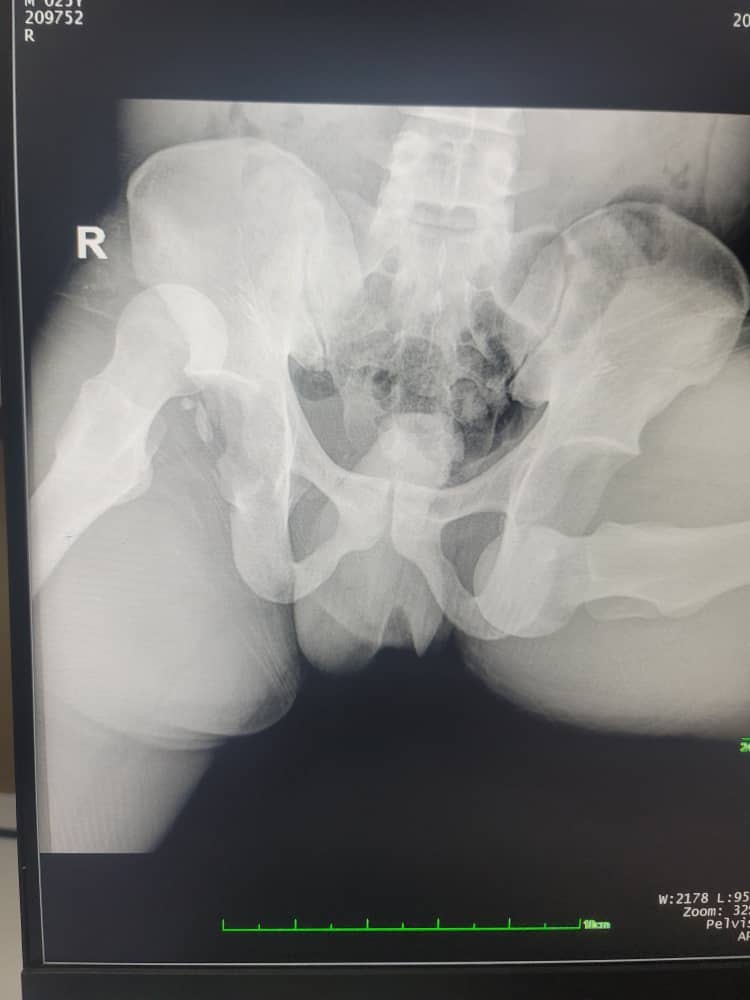

A 32-year-old male patient was brought to the emergency department with complete functional disability of both lower limbs and extensive wounds. According to the bystanders who transported him, he had been struck by a vehicle and had fallen astride a roadside ravine. Both lower limbs were widely abducted, with the left limb in external rotation, abduction, and flexion, whereas the right limb was in external rotation, abduction, and extension at the hips. His buttocks had impacted the ground, acting as a force in this hip position. He did not lose consciousness but was unable to move. On examination, he was unable to move his right upper limb, which exhibited abnormal mobility at the mid-to-distal two-thirds of the right arm, with bone crepitus. Despite these findings, the vascular and neurological assessments of the arm were normal. The left lower limb was flexed, abducted, and externally rotated, with palpable displacement of the femoral head in the Scarpa’s triangle and an empty acetabulum. The lower right limb was extended, abducted, and externally rotated (Fig. 1). The neurovascular examination of both lower limbs was normal.

Figure 1: Clinical presentation of the patient.